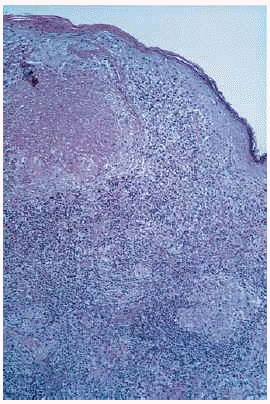

Esta lesión había sido biopsiada en cuatro ocasiones con similares hallazgos histológicos. El principal hallazgo era la presencia en toda la dermis de un denso infiltrado inflamatorio con granulomas constituidos por histiocitos epitelioides y células gigantes multinucleadas en su parte más central y linfocitos en periferia; en varios de ellos existían áreas de caseosis (figs. 2 y 3). Los linfocitos del infiltrado eran monomorfos sin atipias. Se detectaron focos aislados de epidermotropismo, sin franca atipia nuclear en los linfocitos; no se evidenciaron microabcesos de Pautrier; en algunas áreas existía fibrosis laminar en dermis papilar; en algunos cortes se evidenciaron áreas de mucinosis folicular; algunas células gigantes presentaban signos de linfofagocitosis. En el estudio inmuhistoquímico destacaba la expresión de CD3 y CD4 en el 80% del infiltrado linfocitario, del CD68 en las células epiteloides del centro de los granulomas y de la S100 en células dispersas dentro del infiltrado inflamatorio (no en células gigantes). No se observaron signos de elastólisis con la tinción de Van Gieson, ni cuerpos extraños con la luz polarizada, ni microorganismos con las tinciones de Ziehl-Neelsen y PAS. La visión directa de leishmanias, el cultivo para microbacterias y la PCR para Mycobacterium avium intracelulare, Mycobacterium tuberculosis y Mycobacterium leprae fueron negativas. No pudo realizarse estudio de reordenamiento genético.

Fig. 2. Infiltrado en dermis superficial y profunda con formación de granulomas; algunos de los granulomas presentan áreas de necrosis.